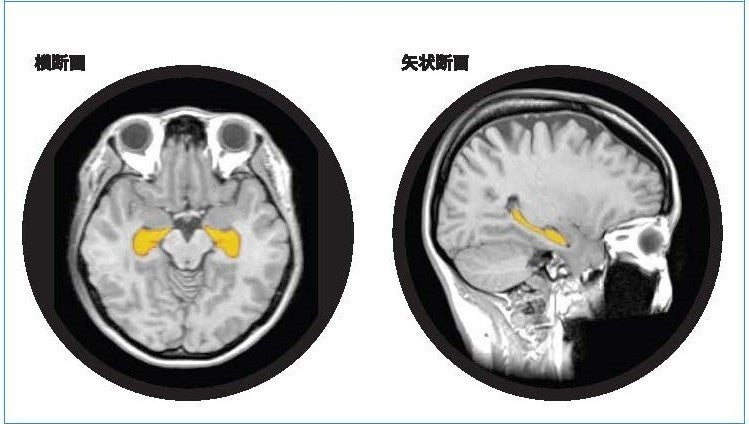

アルツハイマー型認知症は、顕著な脳萎縮を特徴としおり、脳の中でも海馬の萎縮は、20・30代から始まり、生活習慣要因によっては加齢性変化以上に萎縮が加速します。予防として健康なうちより生活習慣の改善をスタートすることがとても大切です。

「BrainSuite®」は、頭部MR画像のAI解析技術等を利用することで海馬の体積や萎縮程度を測定・評価し、同性・同世代と比較した脳の健康状態を可視化します。受検者にはBrainSuite®専用会員ページ「MyPage」が用意され、脳の健康維持・改善方法についてアドバイスを提供します。20代から80代の幅広い年齢層を対象に、「生涯健康脳」の実現を最新の脳医学の観点からサポートするプログラムです。